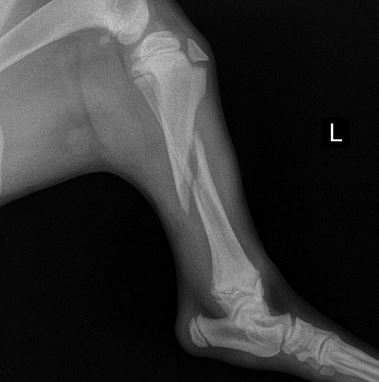

Cirugía traumatológica y ortopédica

Te apoyamos en el diagnóstico y tratamiento, médico y quirúrgico de tu paciente traumatológico/ortopédico

Cirugía ortopédica de rodilla, cadera, hombro y codo. Traumatología ósea apéndicular, columna vertebral, pelvis y cabeza. Osteosíntesis de fracturas con placas óseas, tornillos y fijación esquelética externa.